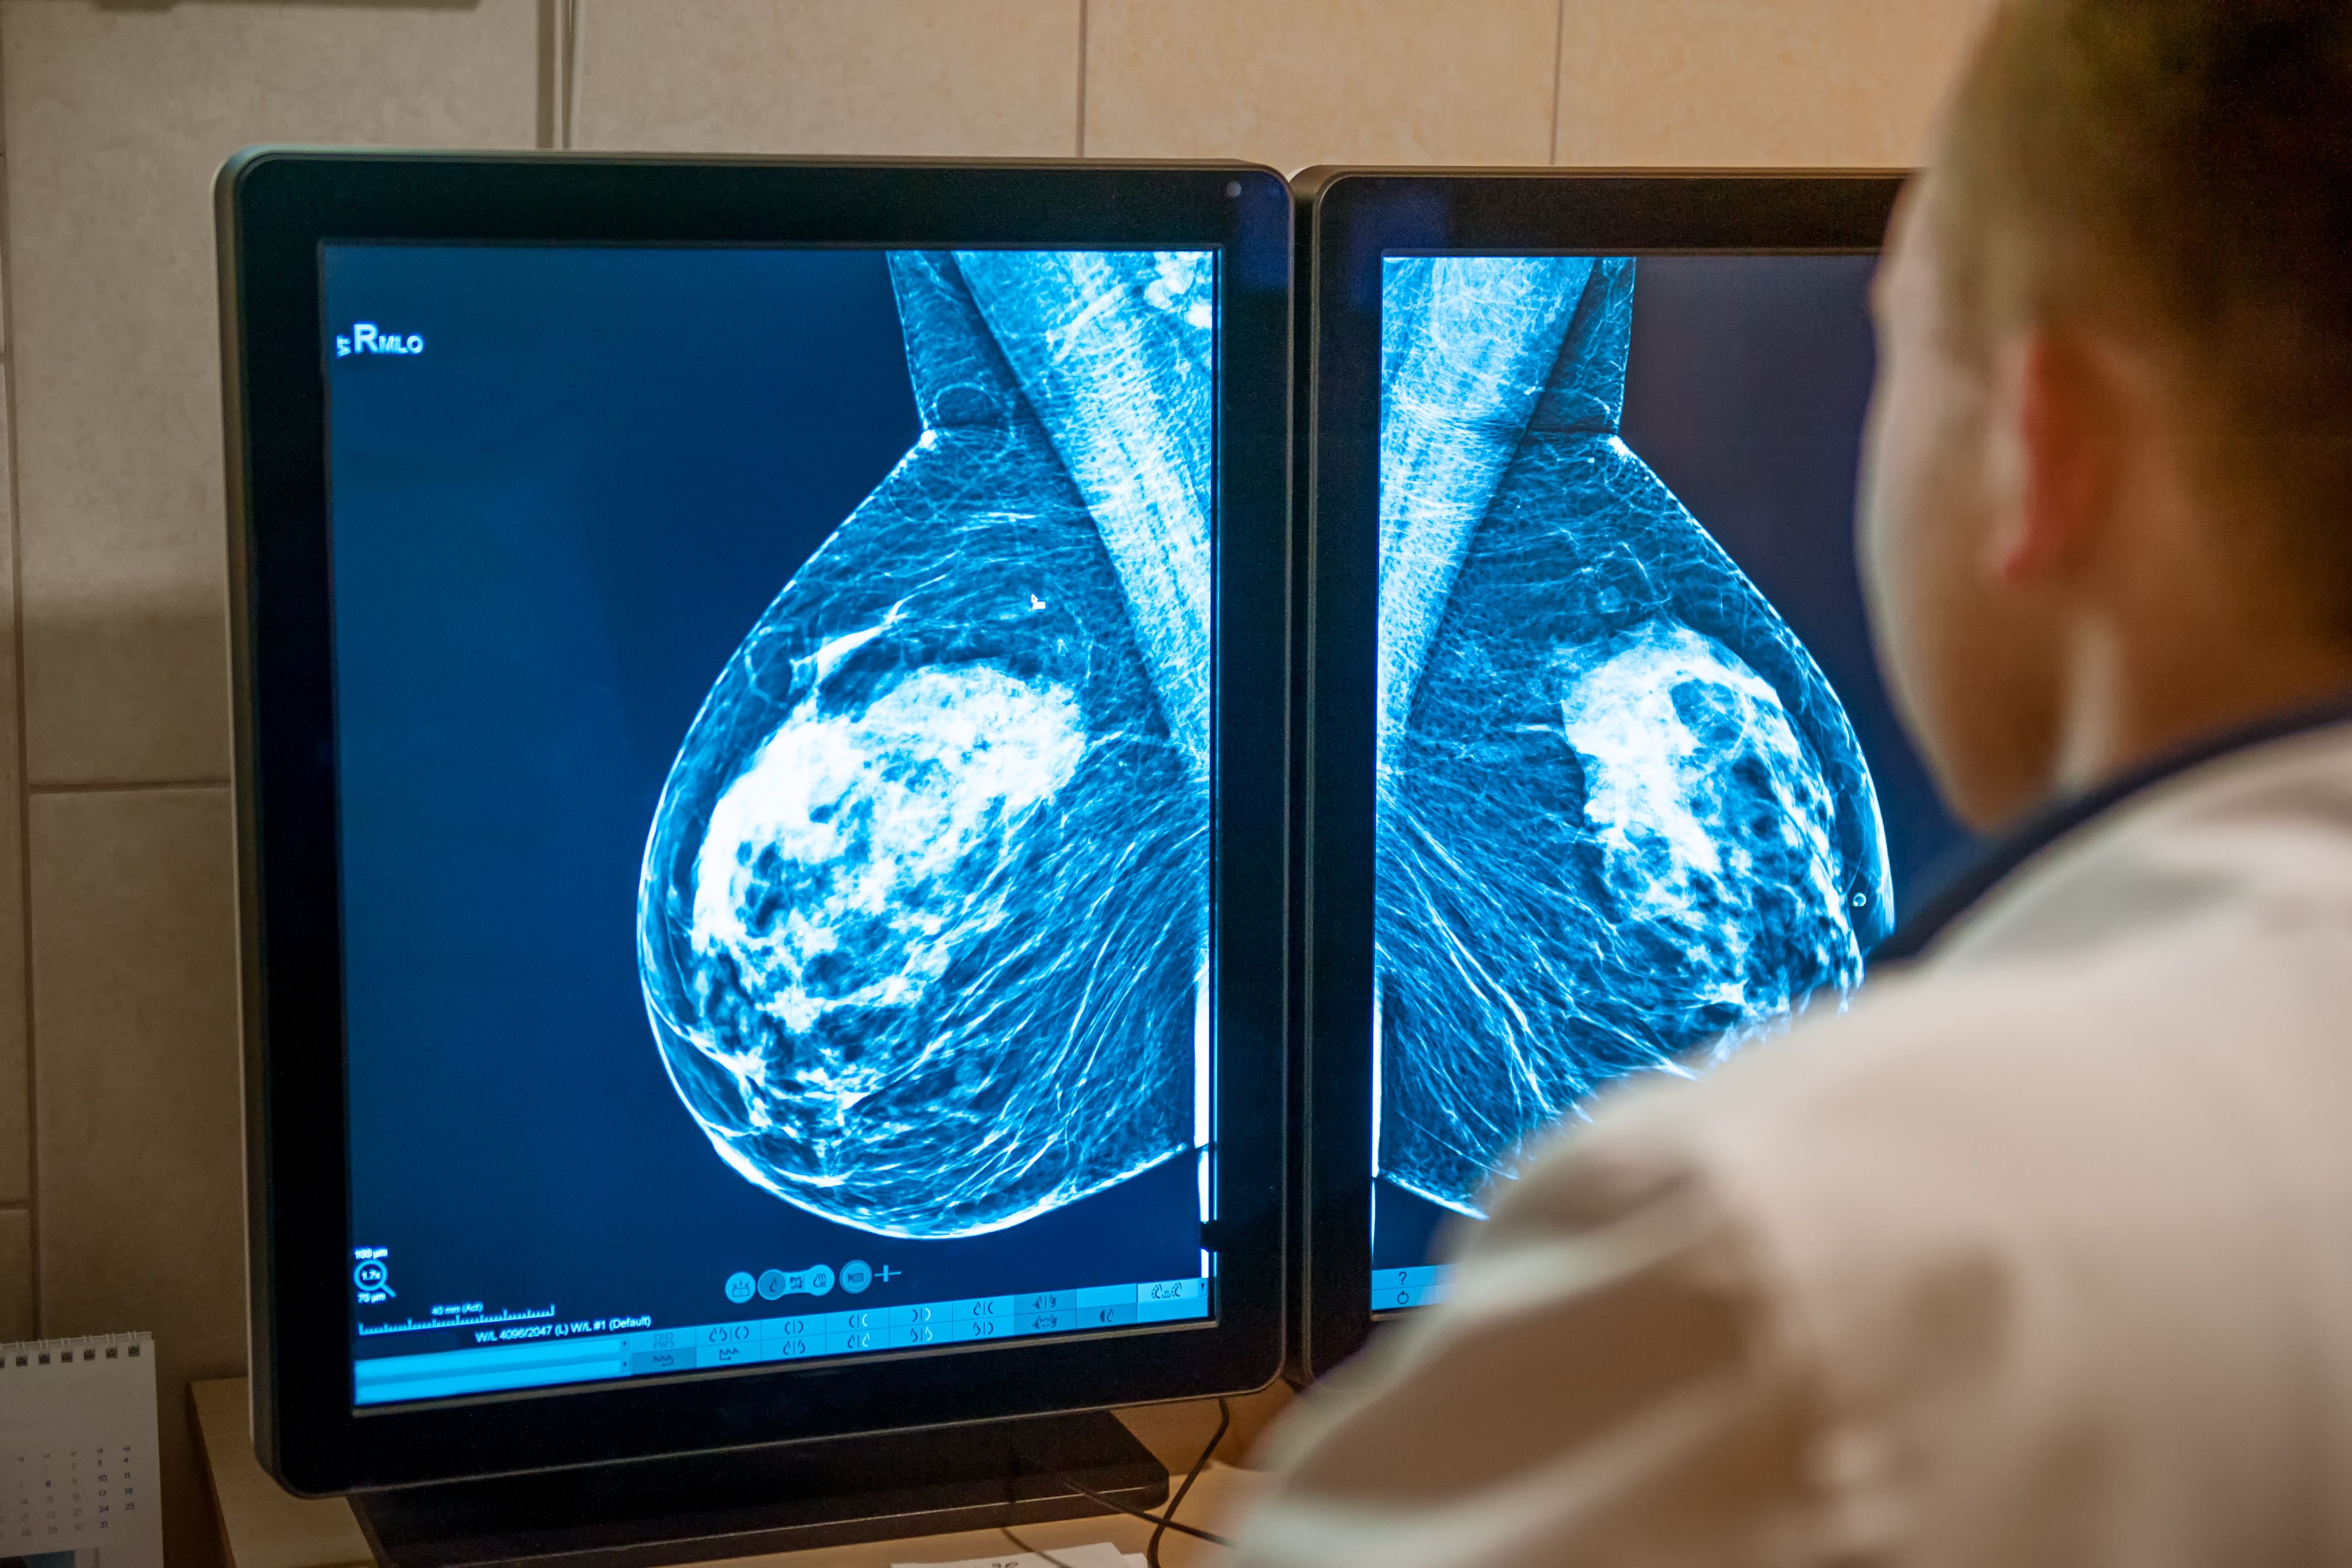

AI-fueled mammography triage software from DeepHealth wins 510(k).

Combination also leads to a reduction in the false-negative rate.